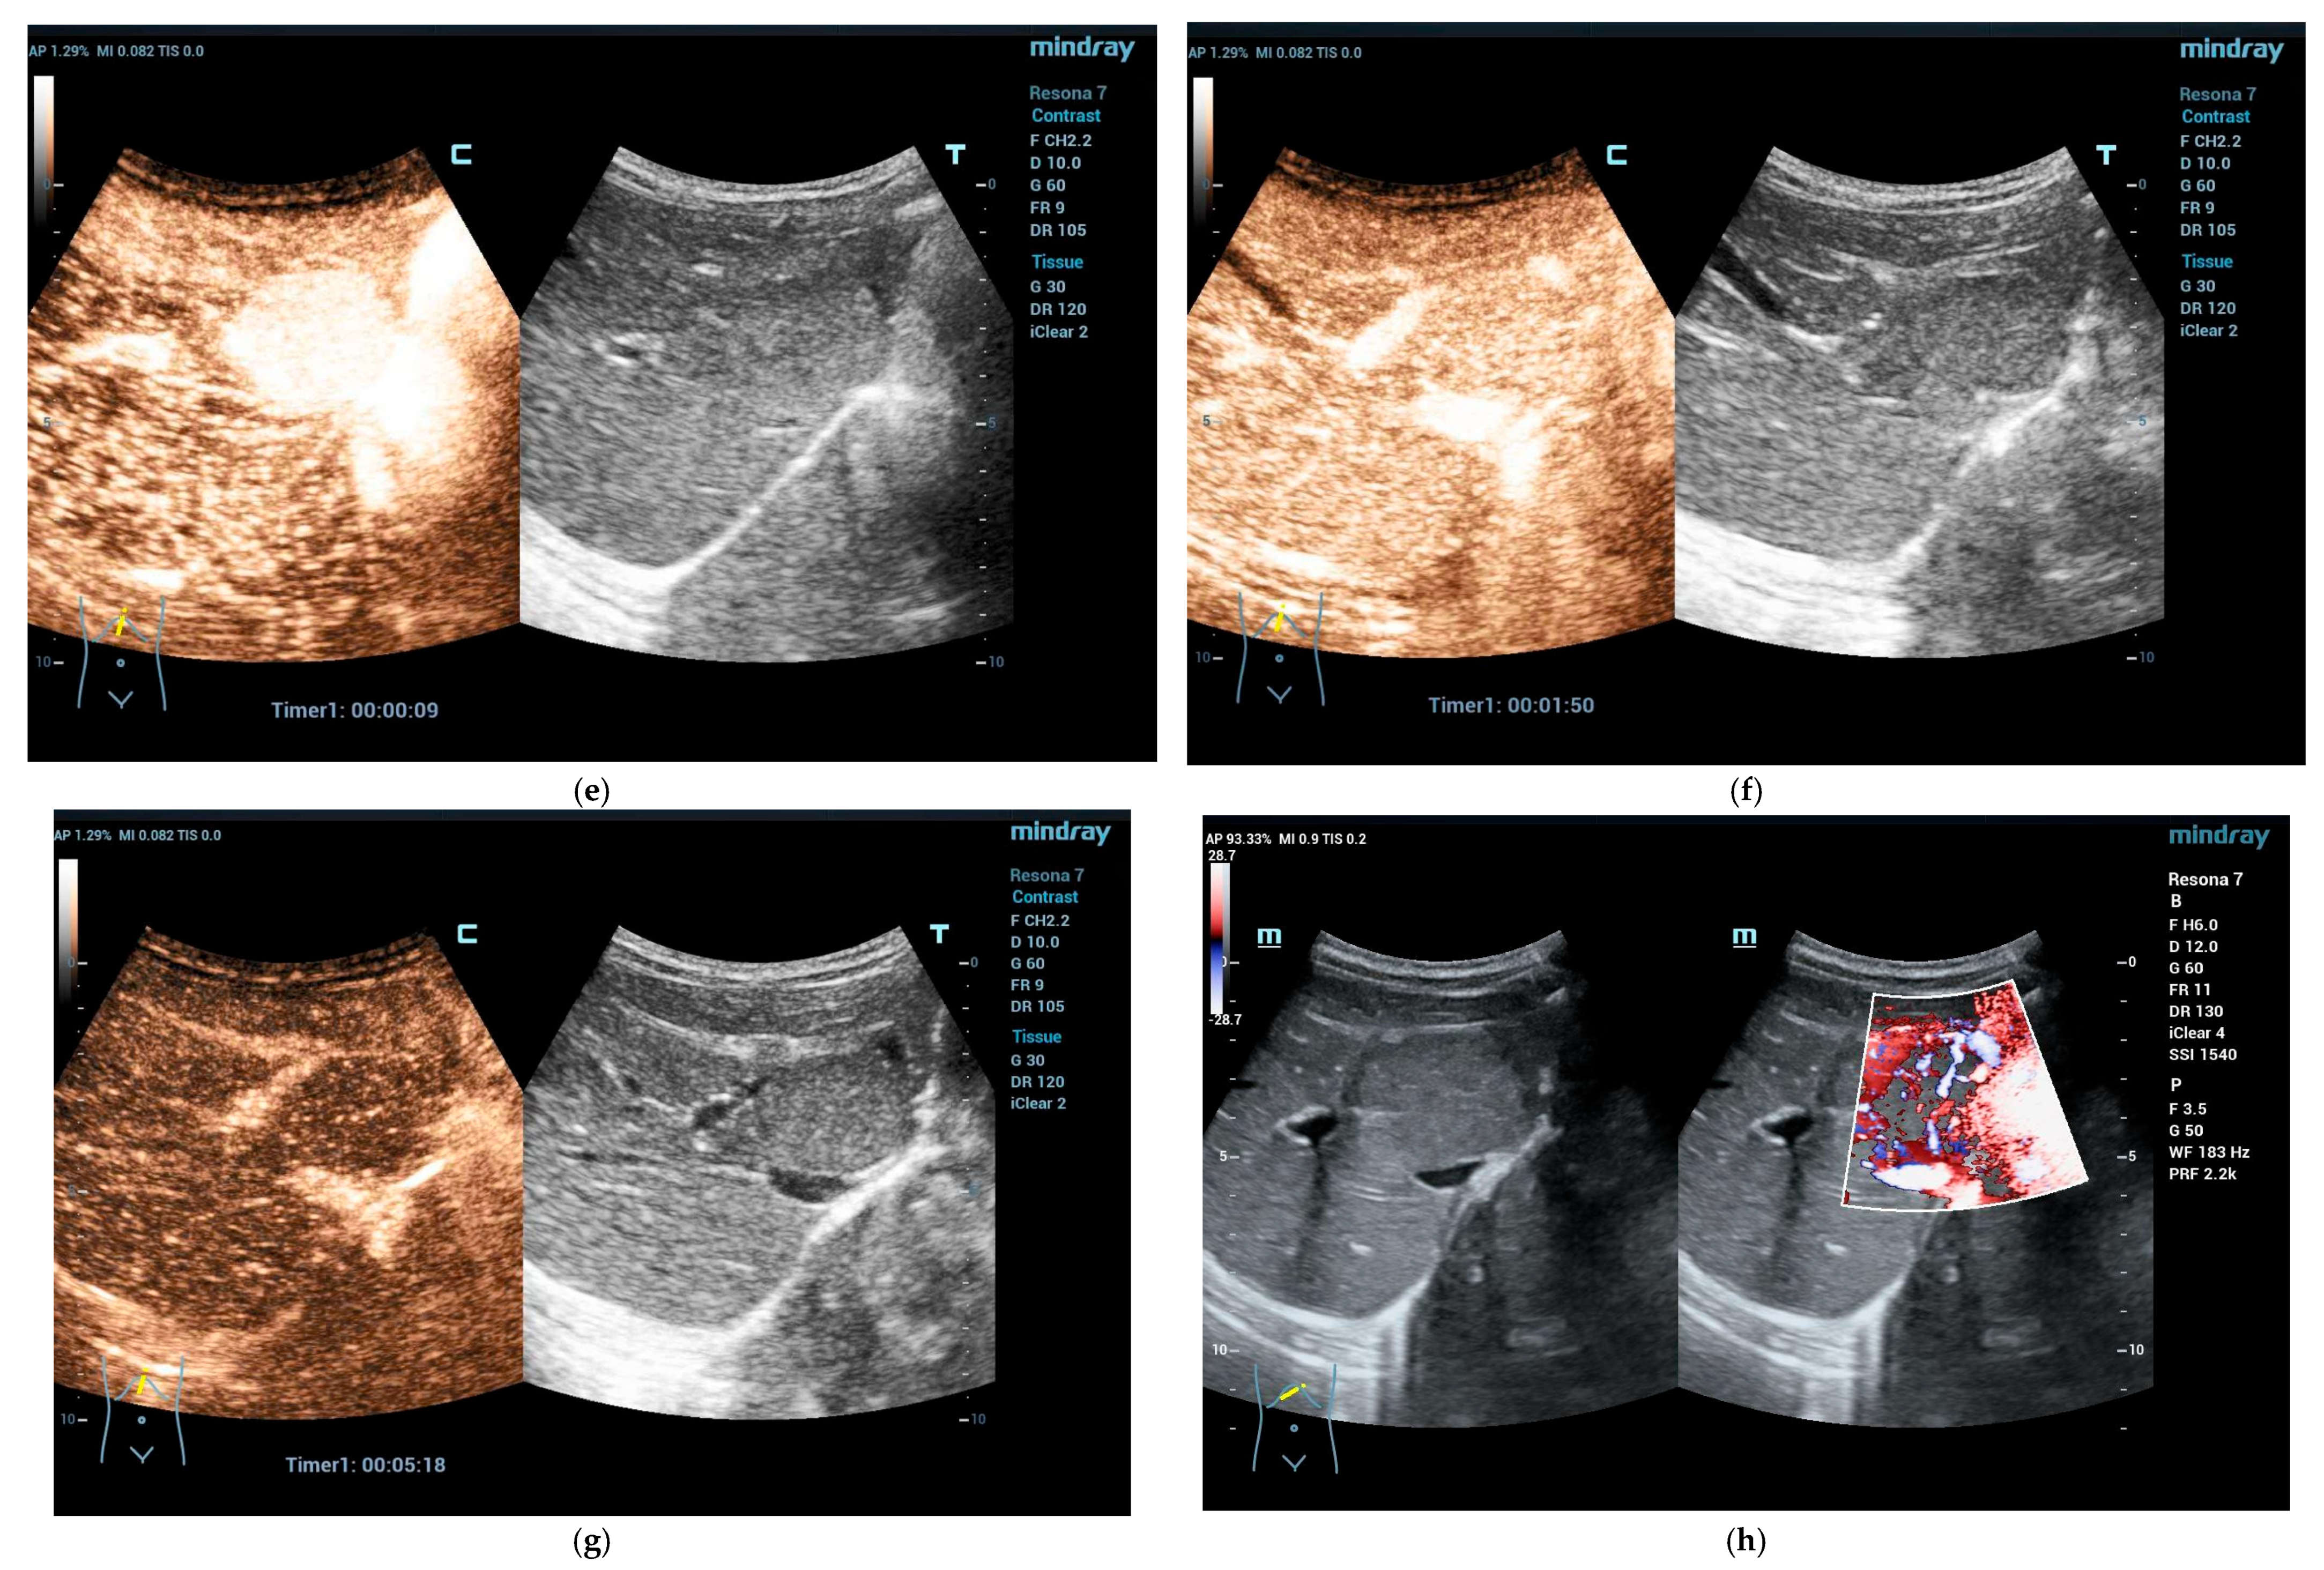

4.3.1. Hepatic Hemangioma

4.3.2. Congenital Hepatic Hemangioma

4.3.3. Infantile Hepatic Hemangioma

- El-Ali, A.M.; McCormick, A.; Thakrar, D.; Yilmaz, S.; Malek, M.M.; Squires, J.H. Contrast-Enhanced Ultrasound of Congenital and Infantile Hemangiomas: Preliminary Results from a Case Series. AJR Am. J. Roentgenol. 2020, 214, 658–664. [Google Scholar] [CrossRef] [PubMed]